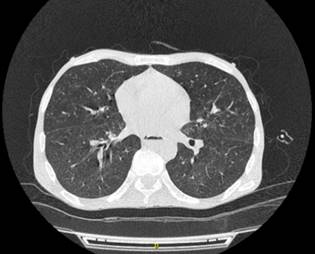

Como apoyo diagnóstico, se realizó baciloscopia que dio positivo y endoscopia de vías digestivas altas, en la que se reportaba mucosa gravemente inflamada con ulceraciones irregulares de hasta 2 cm de profundidad, sucias recubiertas de fibrina, con imágenes de lesiones elevadas irregulares de hasta 1 cm de extensión, sugestiva de tuberculosis gastrointestinal; lo anterior fue confirmado por el estudio histopatológico: esofagitis crónica granulomatosa sugestiva de infección por tuberculosis (Figura 1) y tomografía axial computarizada (TAC) torácica que revela nódulos centrolobulillares con opacidad de árbol en gemación, cuyas características sugieren micobacterias atípicas o típicas, y lesión ocupante de espacio de aspecto infiltrativo a nivel del lóbulo superior derecho (Figura 2). Adicionalmente, en el cuadro hemático se encontró leucocitos 5040/mm3, neutrófilos: 70%, linfocitos: 19%, hemoglobina 9,6:%, plaquetas: 271 000/mm3, tiempo de protrombina: 18 segundos, índice internacional normalizado (INR): 1,45, nitrógeno ureico sanguíneo (BUN): 12 mg/dL, creatinina: 0,6 mg/dL, aspartato-aminotransferasa (AST): 123 UI/L, alanina-aminotransferasa (ALT): 44 UI/L, lactato-deshidrogenasa (LDH): 129 UI/L, PCR: 2,07; pruebas complementarias: VIH 191 (positivo), VHC (no reactivo), VHB 0,4 (negativo), treponema (negativo), toxoplasma inmunoglobulina M (IgM) 0,2 (negativo).